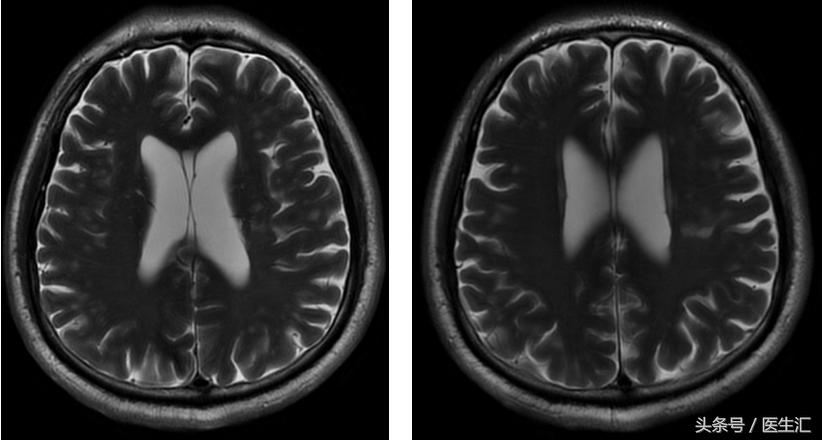

影像检查